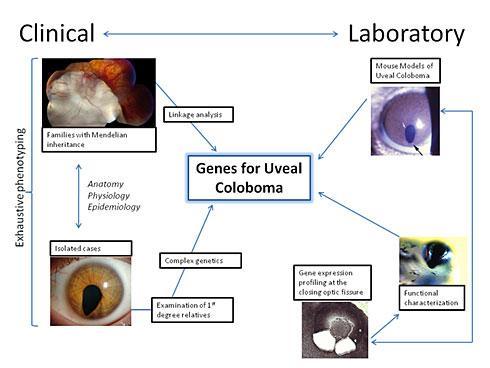

Uveal coloboma is a potentially blinding, developmental abnormality of the eye caused by failure of the optic fissure to close during the 5th week of human gestation. The purpose of our clinical and basic research is to better understand the genetic and developmental mechanisms of optic fissure closure. Our short-term goal is to provide better diagnostics and genetic counseling for our patients; our long-term goal is to find preventions and/or treatments for this condition. Our approach is summarized in the following figure:

Our clinical studies are focused on understanding the coloboma phenotype more deeply, including deep ocular and systemic phenotyping, where appropriate, leveraging the unparalleled resources of the NIH Clinical Center. Genetic analysis using the tools of whole exome/whole genome sequencing are being undertaken to identify causative genes and improve genetic counseling for patients with coloboma see and what, if any, associated clinical conditions they might have.

A complementary approach to understanding genes important in optic fissure closure in humans is the laboratory use of animal models. We use mouse and zebrafish models to better understand how genes are regulated during the course of optic fissure closure. Specific mutant mouse strains are also being investigated to discover genes that might cause coloboma in humans. These studies have identified that two zinc finger proteins, Nlz1 and Nlz2, regulate optic fissure closure, perhaps through a Pax2-dependent mechanism. We are currently trying to understand the developmental role of these and other genes from our screen in the normal process of optic fissure closure and to search for causative mutations in humans.